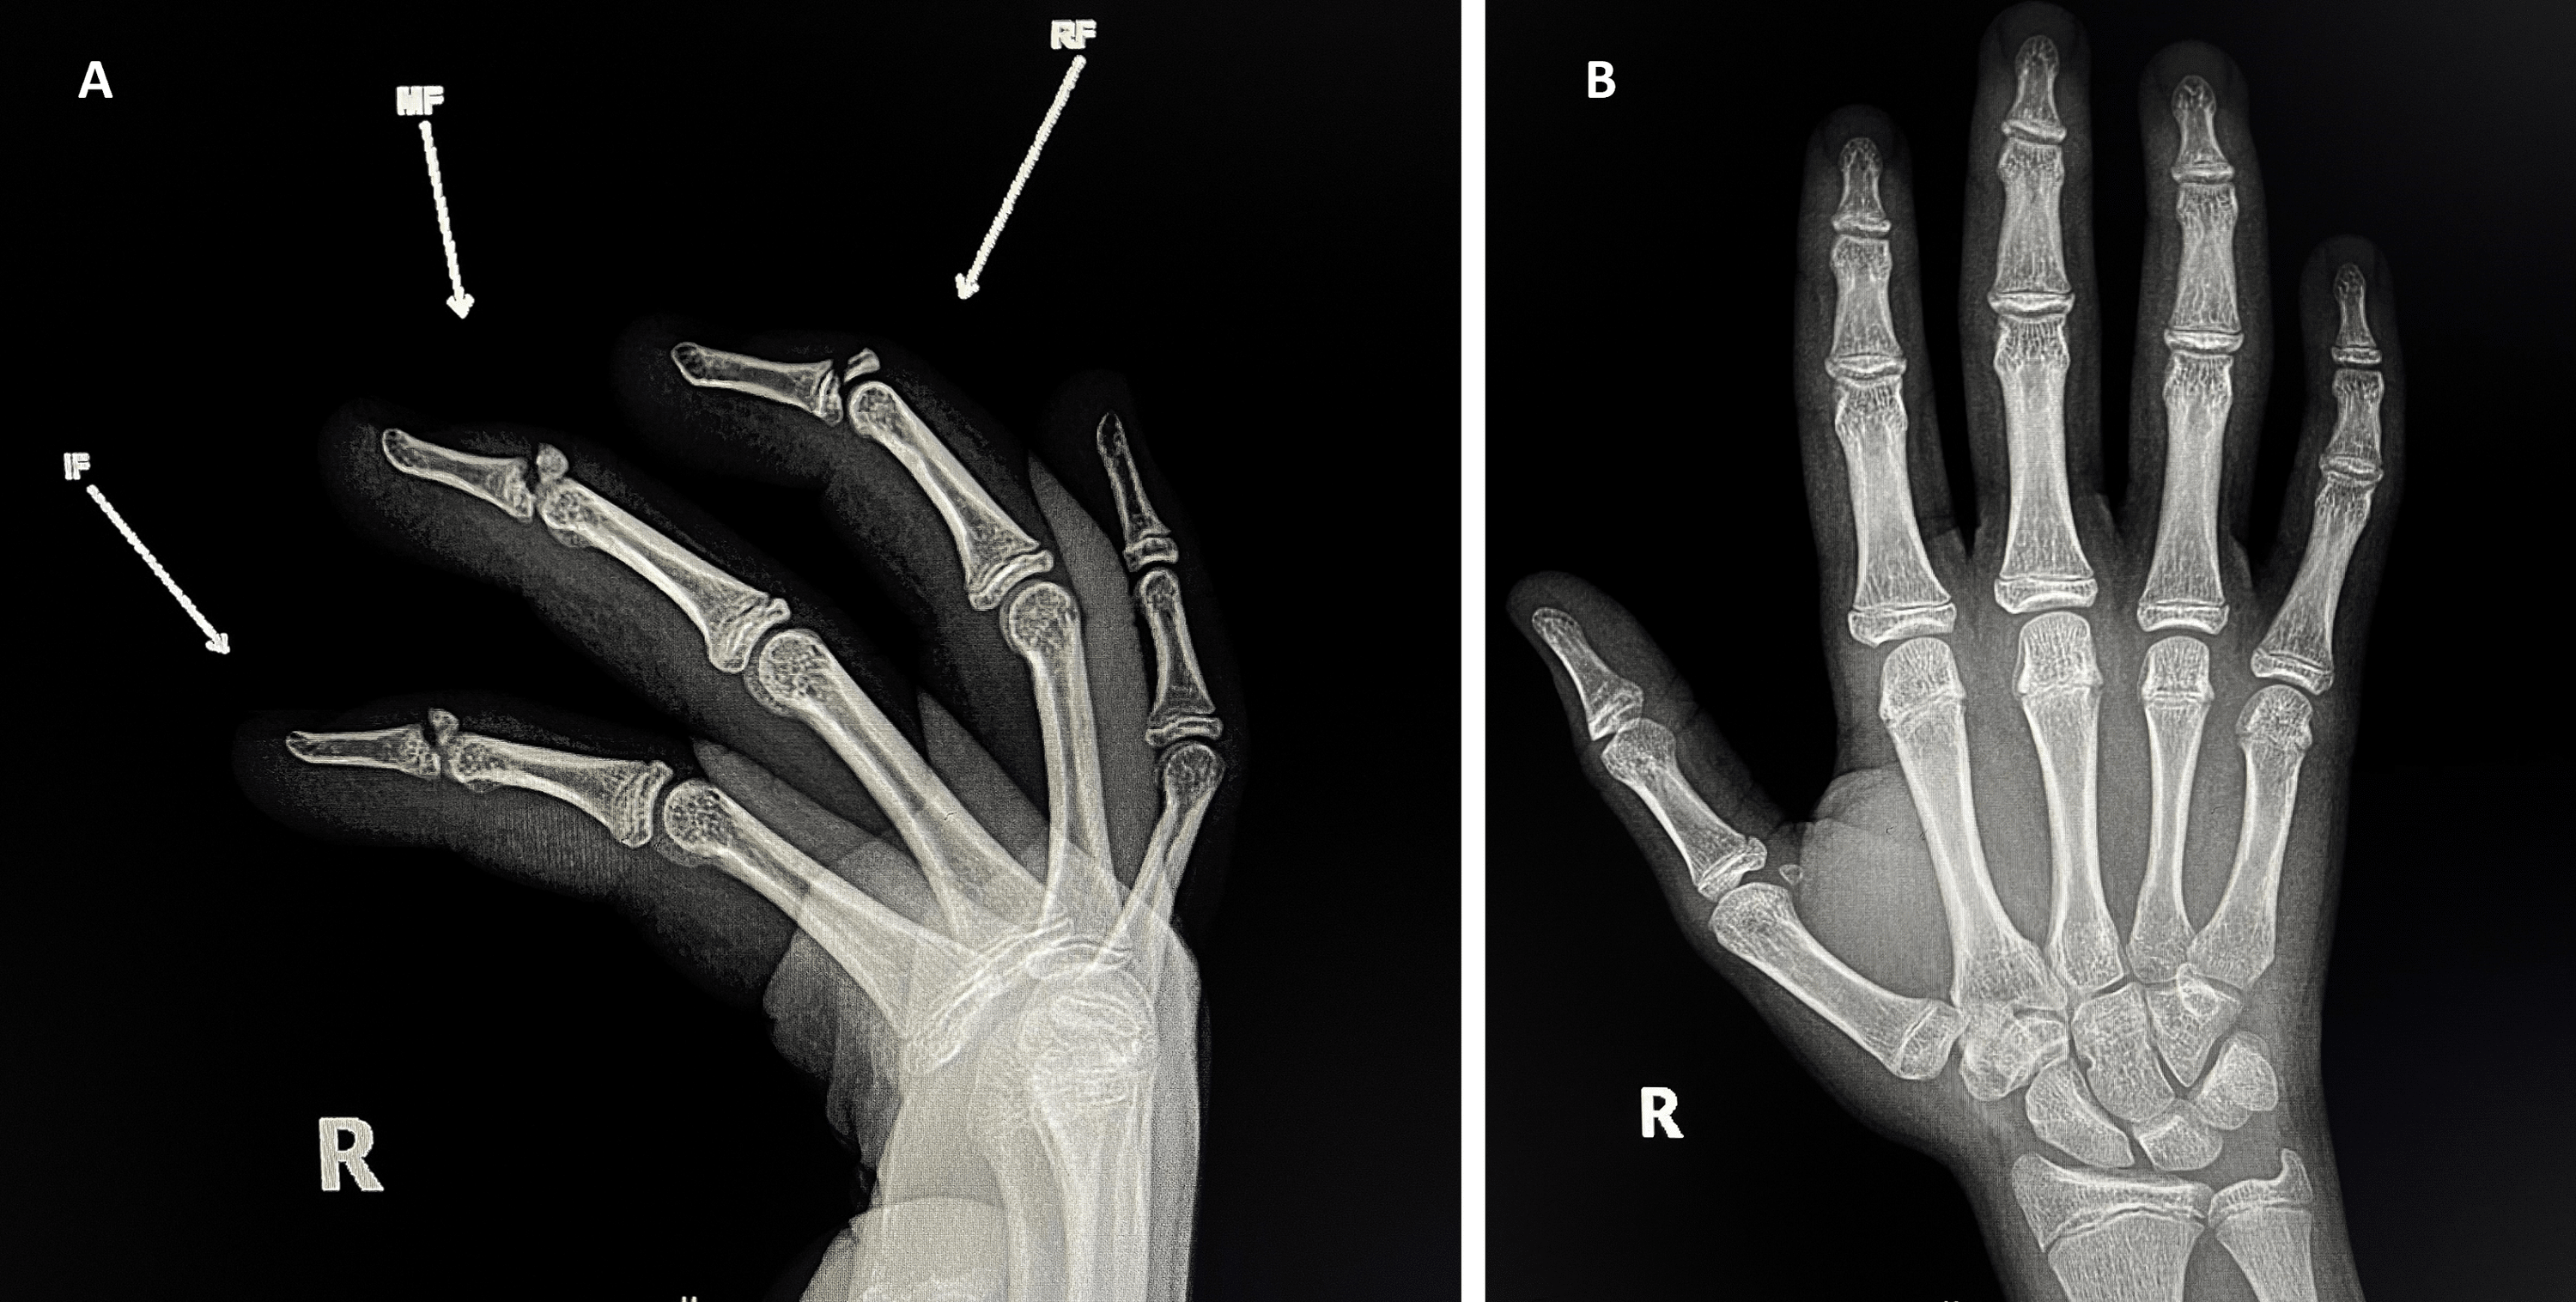

Cureus Multiple Bony Mallet Finger Injuries in One Hand of a 14Year Mallet Finger Xray Posteroanterior (pa) and lateral radiographs centered at the distal interphalangeal (dip) joint of the affected finger. Look for evidence of an avulsion fracture on the dorsal aspect of the base of the distal phalanx (=bony mallet). Causes include getting a finger (usually the fourth, or ring, finger) caught in an opponent’s jersey while making a tackle in football or rugby.. Mallet Finger Xray.

Mallet Finger Autofusion in Adolescent PostPin Fixation Surgery A Mallet Finger Xray Causes include getting a finger (usually the fourth, or ring, finger) caught in an opponent’s jersey while making a tackle in football or rugby. Mallet finger is a finger deformity caused by disruption of the terminal extensor tendon distal to dip joint diagnosis is made clinically when the distal phalanx rests at ~45° of flexion. Refers to damage in the. Mallet Finger Xray.